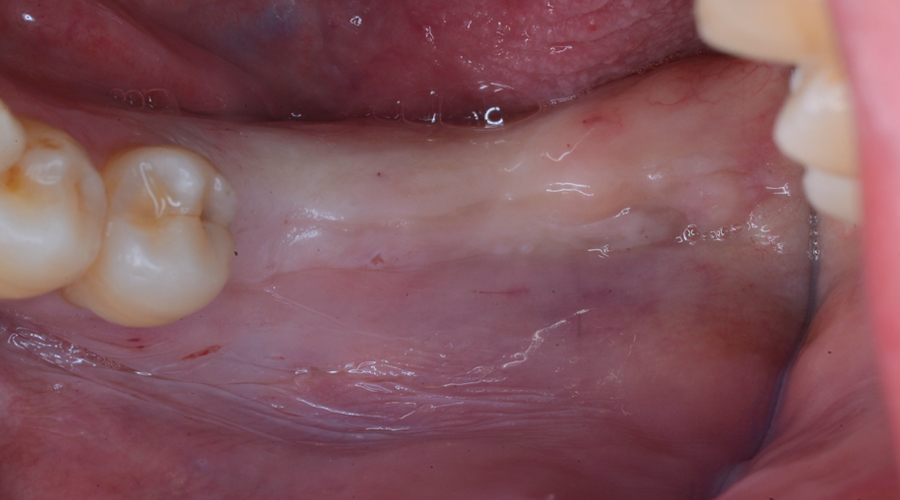

治療前

治療内容欠損部位に対して、人工歯根を埋入し上部構造として補綴物をかぶせる治療です。

治療に伴うリスク治療後の口腔管理が不適切な場合、埋入したインプラント周囲に感染・炎症を起こし、脱落する可能性がございます。